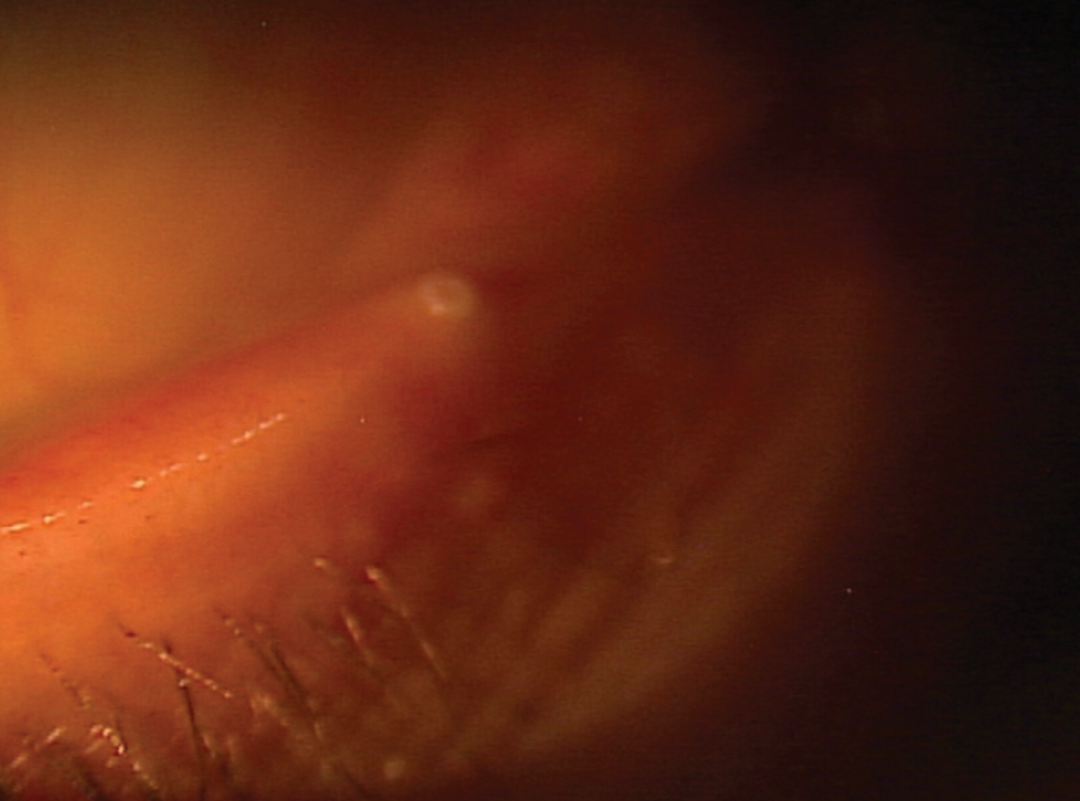

图3 泪膜皂化是睑缘炎和睑板腺功能障碍等疾病中细菌过度生长的关键指标

眼睑清创、睑板腺挤压和微睑缘去角质是管理前部睑缘炎和睑板腺功能障碍的重要初级门诊治疗方法。眼睑清创涉及使用金铲温和机械去除睑缘的生物膜、角化上皮和碎屑,恢复腺体开口并促进睑脂流动。该治疗与手动睑板腺挤压相结合,被推荐为初次干眼症评估和随访期间的一线干预措施。它们共同提供了关于腺体阻塞严重程度、生物膜负荷和睑脂质量的关键诊断见解,有助于制定进一步的治疗方案。

微睑缘去角质作为一种先进的清创形式,通过彻底去除睑缘角质,帮助清除生物膜和前部睑缘炎积聚,从而提高疗效[38]。一项临床研究表明,微睑缘去角质显著改善了中重度睑板腺功能障碍患者的主观症状,提高了睑板腺分泌质量,并减少了炎症生物标志物如基质 MMP-9[39]。微睑缘去角质是治疗睑板腺功能障碍和前部睑缘炎患者的早期良好工具。